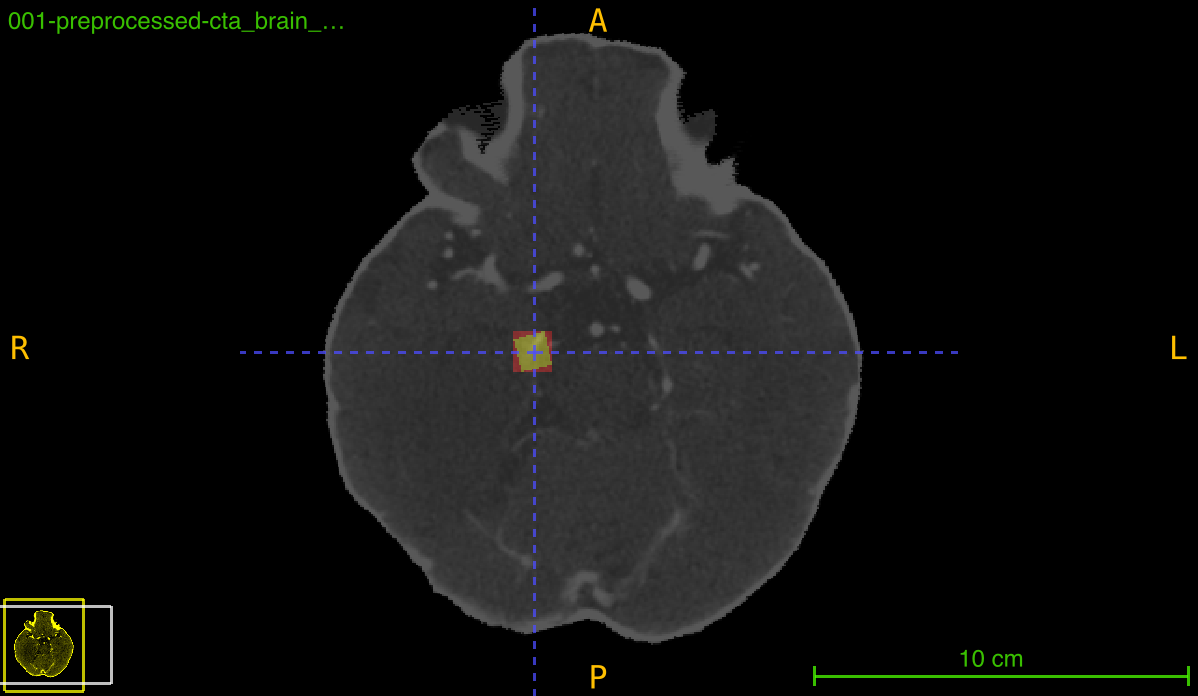

Visualize Transformed Annotations

Create visual comparison of annotations:

from nidataset.preprocessing import register_annotation

import nibabel as nib

import matplotlib.pyplot as plt

import numpy as np

# Register with recalculation

register_annotation(

annotation_path="lesion_bbox.nii.gz",

transform_path="transforms/transformation.tfm",

registered_path="registered/scan_registered.nii.gz",

output_path="registered/bbox_recalc.nii.gz",

recalculate_bbox=True

)

# Register without recalculation

output_path="registered/bbox_deformed.nii.gz",

recalculate_bbox=False

# Load for visualization

scan = nib.load("registered/scan_registered.nii.gz").get_fdata()

bbox_recalc = nib.load("registered/bbox_recalc.nii.gz").get_fdata()

bbox_deformed = nib.load("registered/bbox_deformed.nii.gz").get_fdata()

# Select middle slice

mid_slice = scan.shape[2] // 2

# Create visualization

fig, axes = plt.subplots(1, 3, figsize=(18, 6))

# Original scan

axes[0].imshow(scan[:, :, mid_slice], cmap='gray')

axes[0].set_title('Registered Scan', fontsize=14)

axes[0].axis('off')

# With recalculated bbox

axes[1].imshow(scan[:, :, mid_slice], cmap='gray')

axes[1].imshow(bbox_recalc[:, :, mid_slice], cmap='Reds', alpha=0.4)

axes[1].set_title('Recalculated BBox\n(Axis-aligned)', fontsize=14)

axes[1].axis('off')

# With deformed bbox

axes[2].imshow(scan[:, :, mid_slice], cmap='gray')

axes[2].imshow(bbox_deformed[:, :, mid_slice], cmap='Blues', alpha=0.4)

axes[2].set_title('Deformed BBox\n(Preserves shape)', fontsize=14)

axes[2].axis('off')

plt.tight_layout()

plt.savefig('annotation_comparison.png', dpi=150, bbox_inches='tight')

print("Visualization saved: annotation_comparison.png")